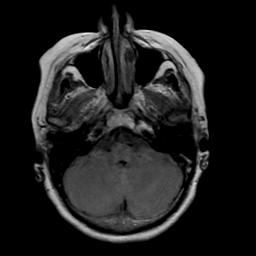

Stroke: proton density-weighted MR #2 -- Slice #4

[Home][Help][Clinical] Slice 4